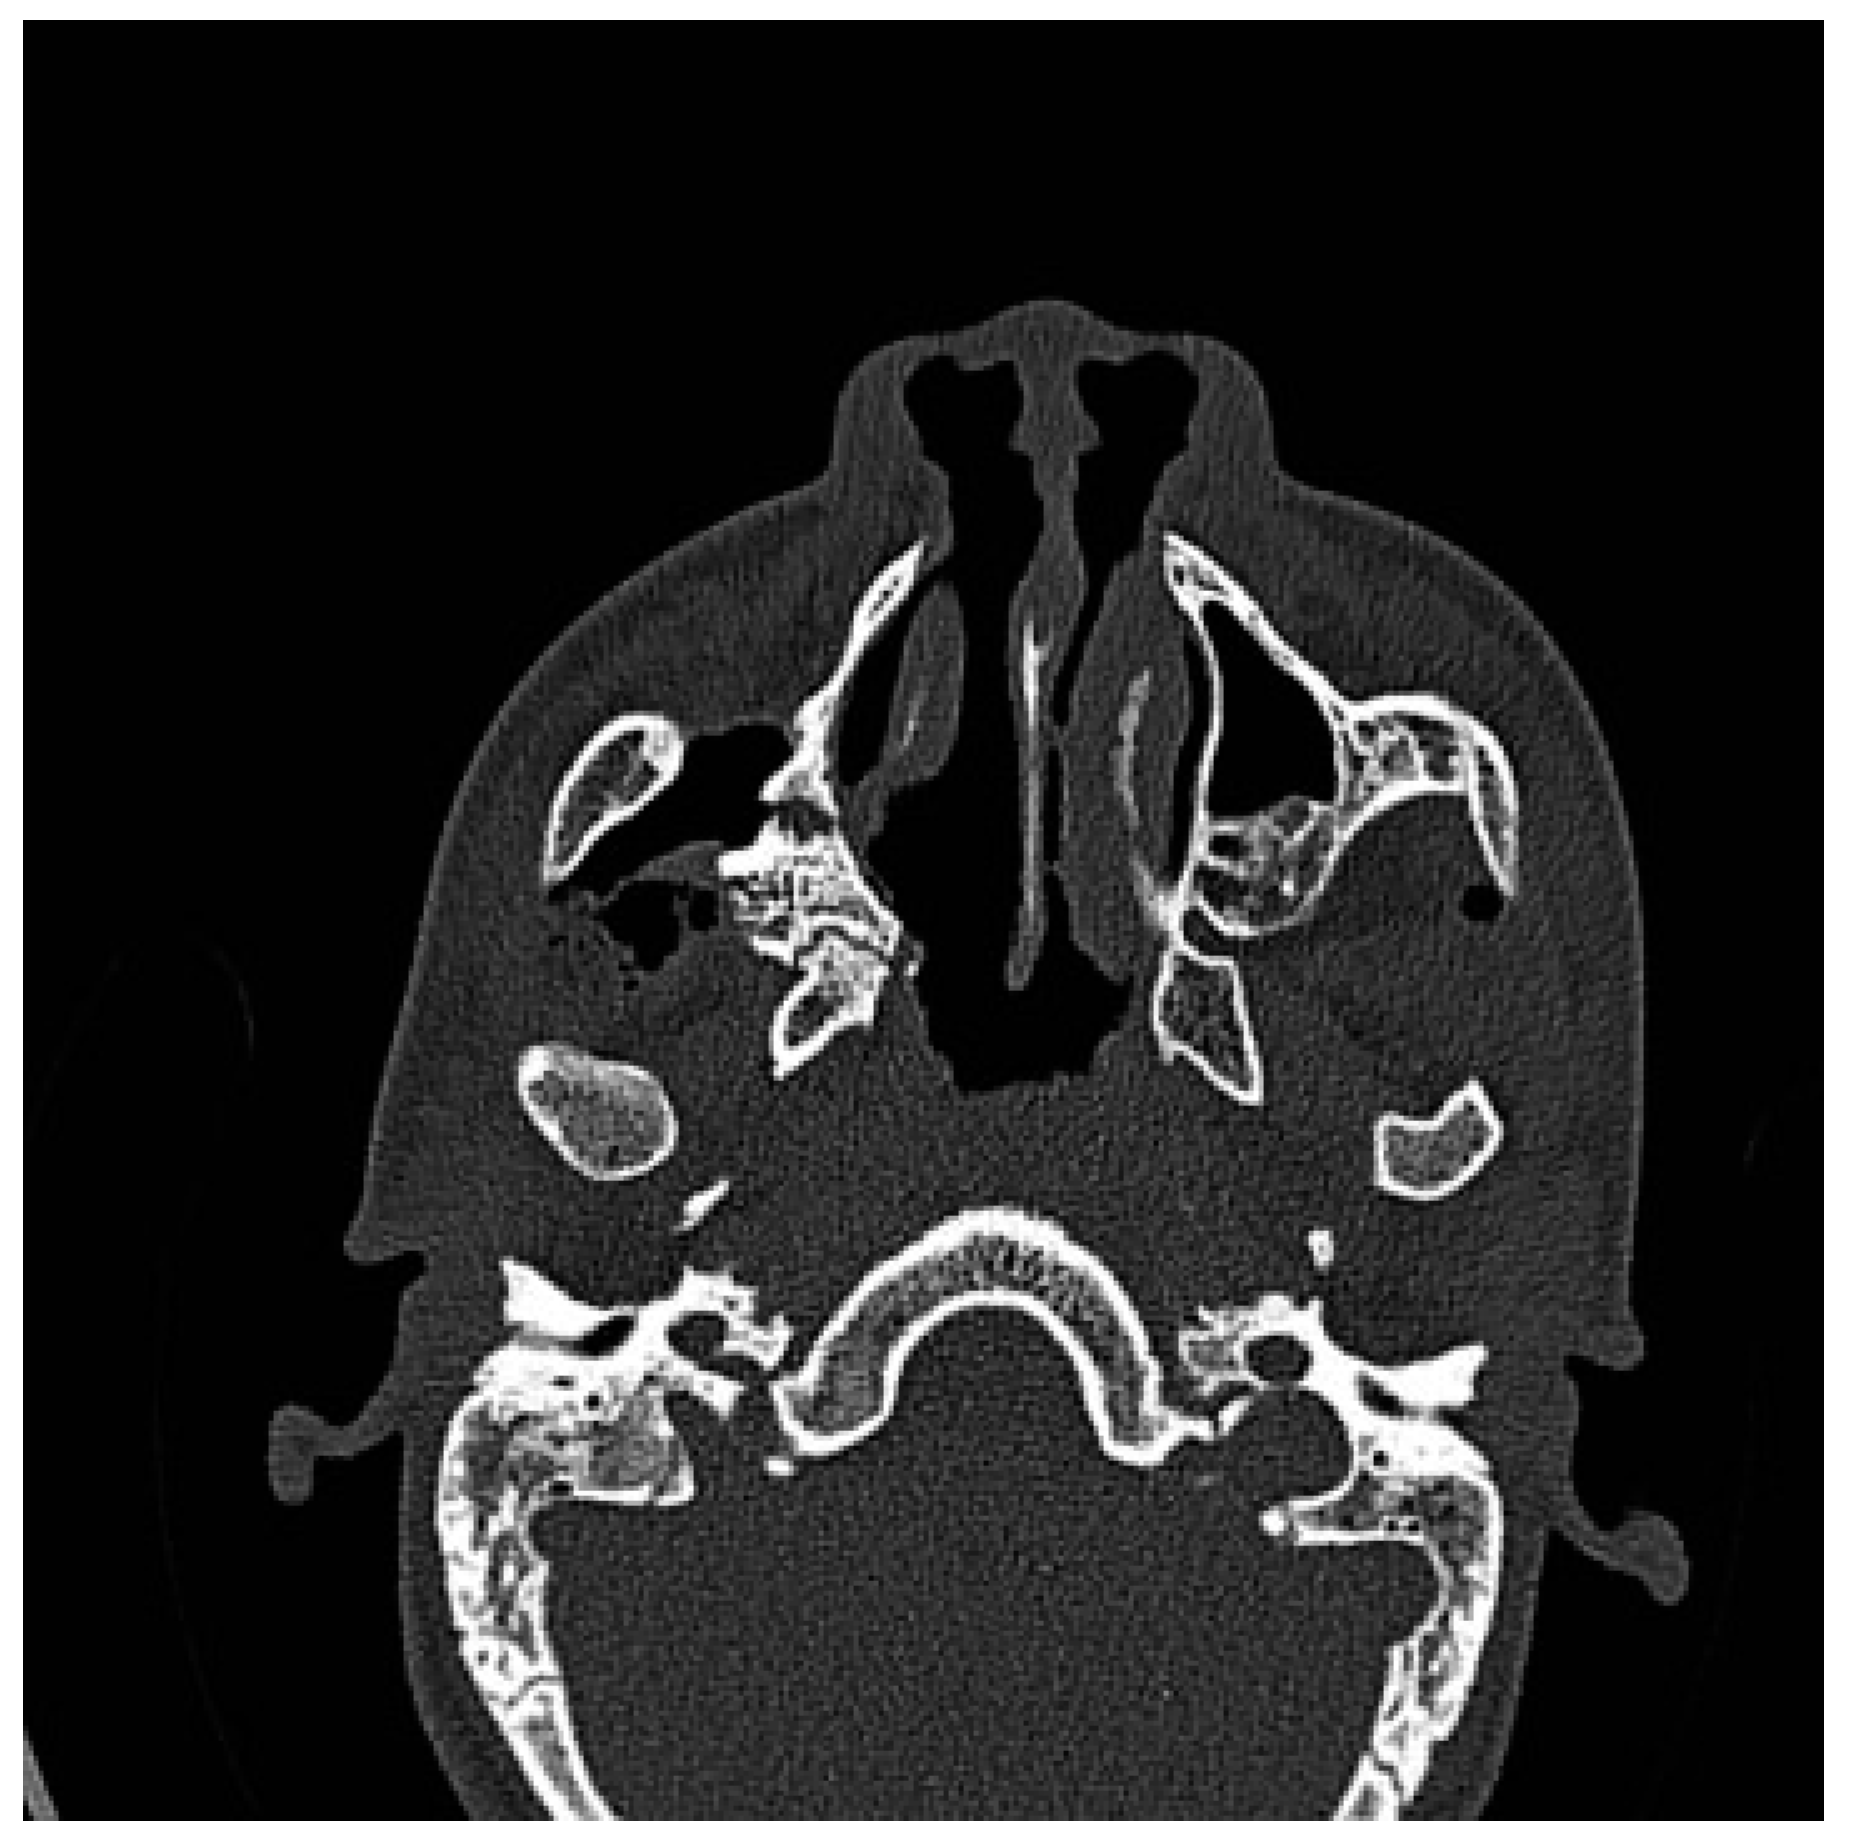

Figure 1. Preoperative CT scan. Axial view: right maxillomandibular fusion.

A CT scan of the head with 3D reconstruction (Figure 1, Figure 2, Figure 3, Figure 4 and Figure 5) confirmed a maxillomandibular fusion associated with a cleft palate, agenesis of the right turbinate, and right hemifacial microsomia (Laster type 2b syngnathia). Both temporomandibular joints (TMJs) were normal and showed no bony ankylosis (fibrous ankylosis could not be excluded with the given data).